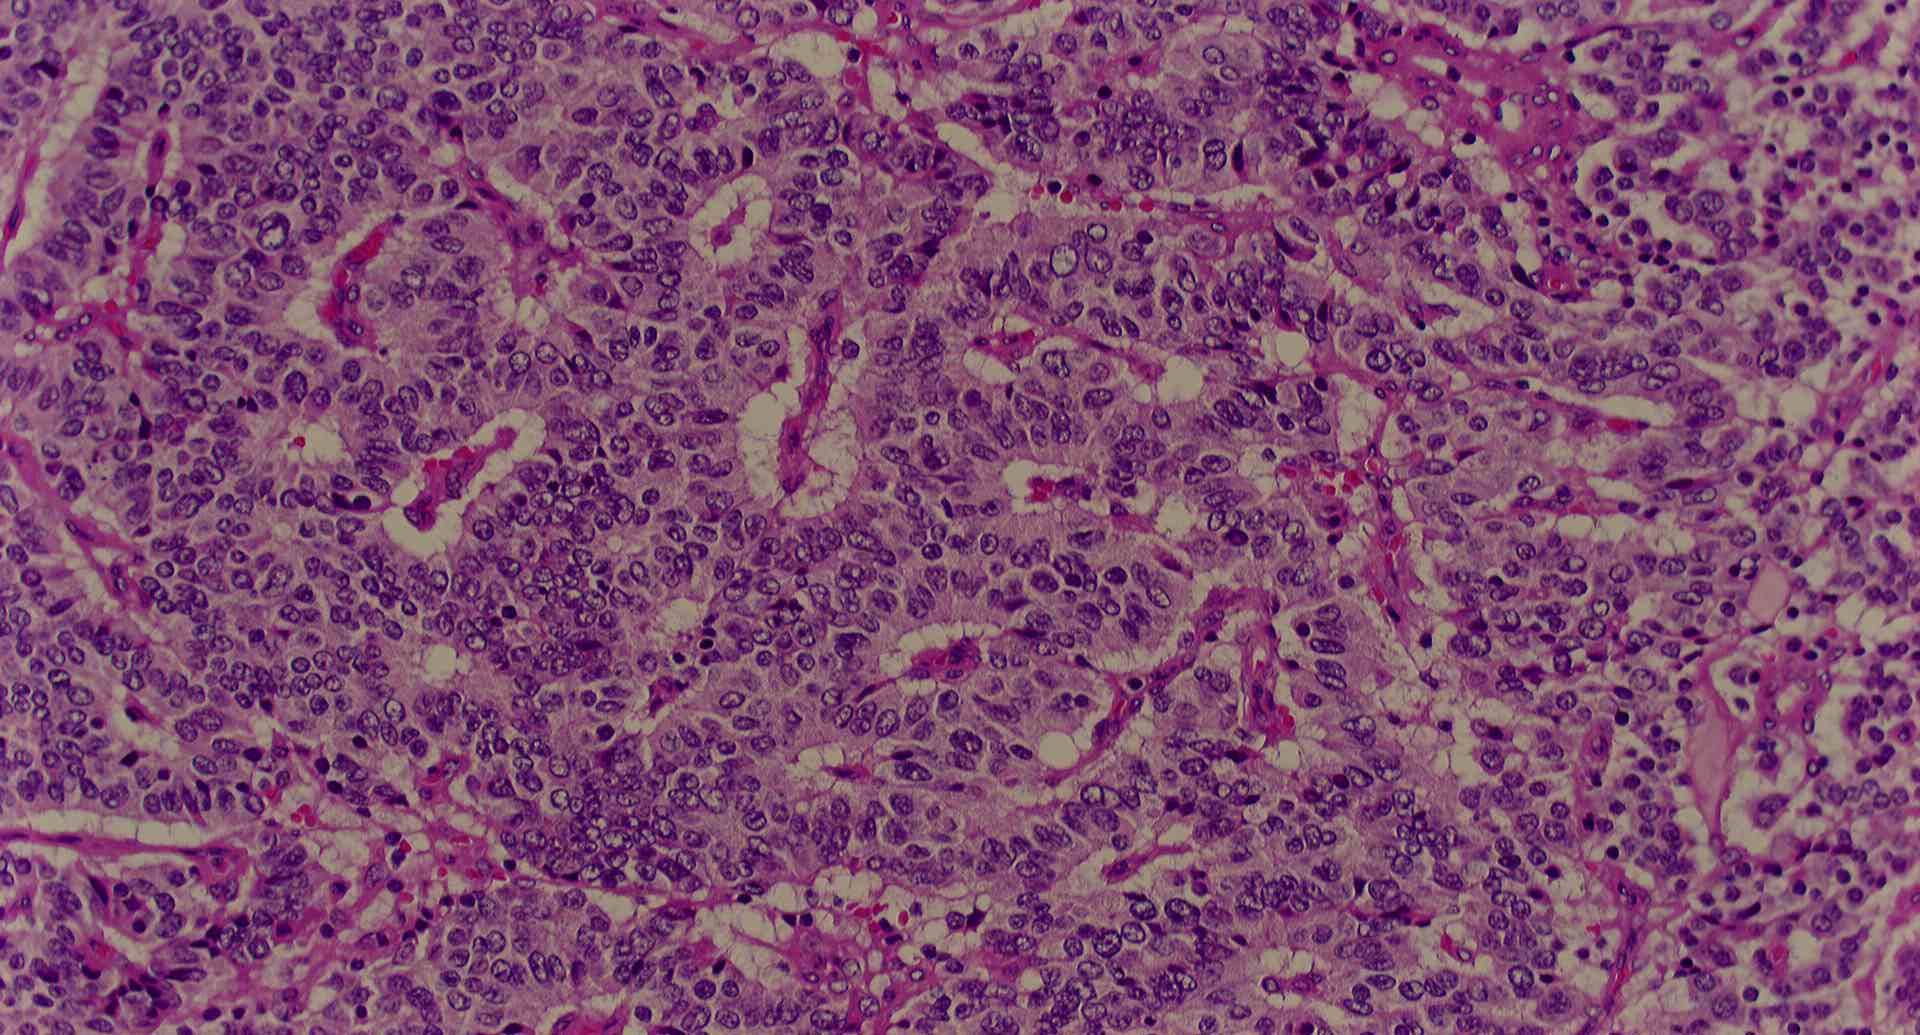

標本17

標本17の説明